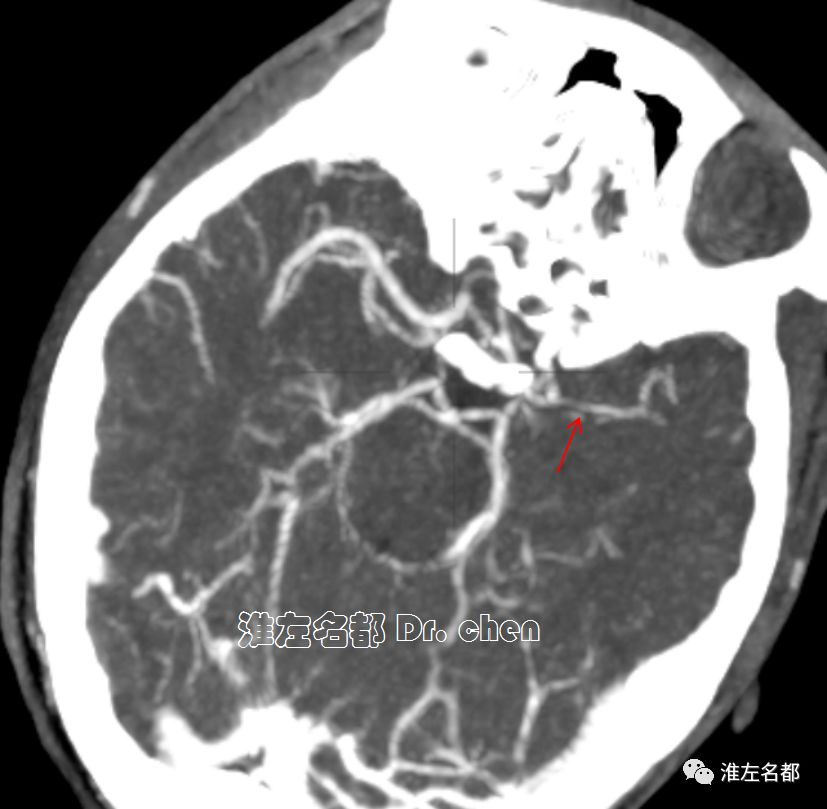

△脑CTP静脉早期多平面重建:左侧大脑中动脉主干显影细小(红箭)